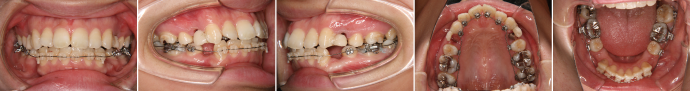

| 主訴 | 前歯が出ている |

| 年齢・性別 | 35歳 / 女性 |

| 治療方針 | 叢生も前歯の突出も大きいケース。小臼歯抜歯だけでは改善できないため、大臼歯の抜歯も行なった。 |

| 抜歯部位 | 上下顎左右小臼歯、左上第1大臼歯(計5本) |

| 使用装置 | マルチブラケット装置 |

| 治療期間 | 36か月 |

| リテーナー | 上顎インビジブル、フィックス、下顎インビジブル |

| 費用 | 885,000円(税別) |